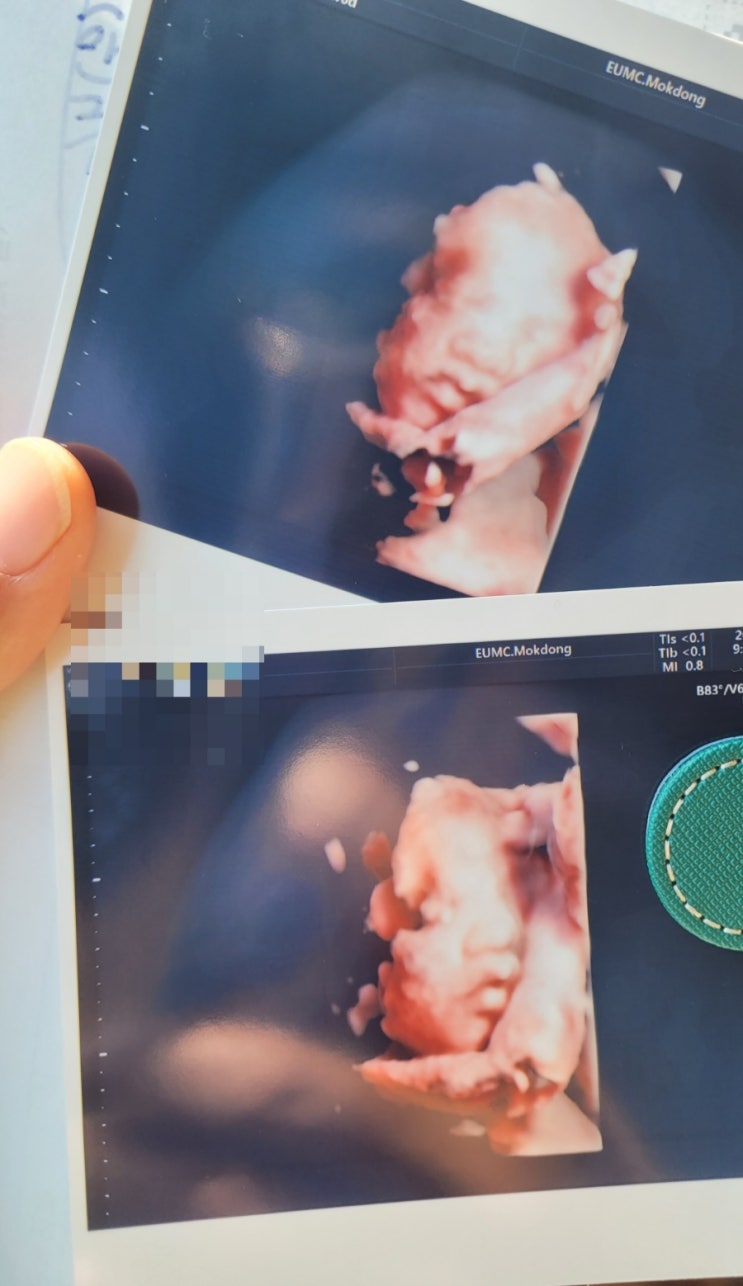

임신일기24- 네...삐빅.... 치질입니다.....

임신 30주차 치밍아웃의 시간이다.... 좀 괜찮아진 건가 싶었는데 며칠 연속으로 볼일보고 나면 변기물이 ...